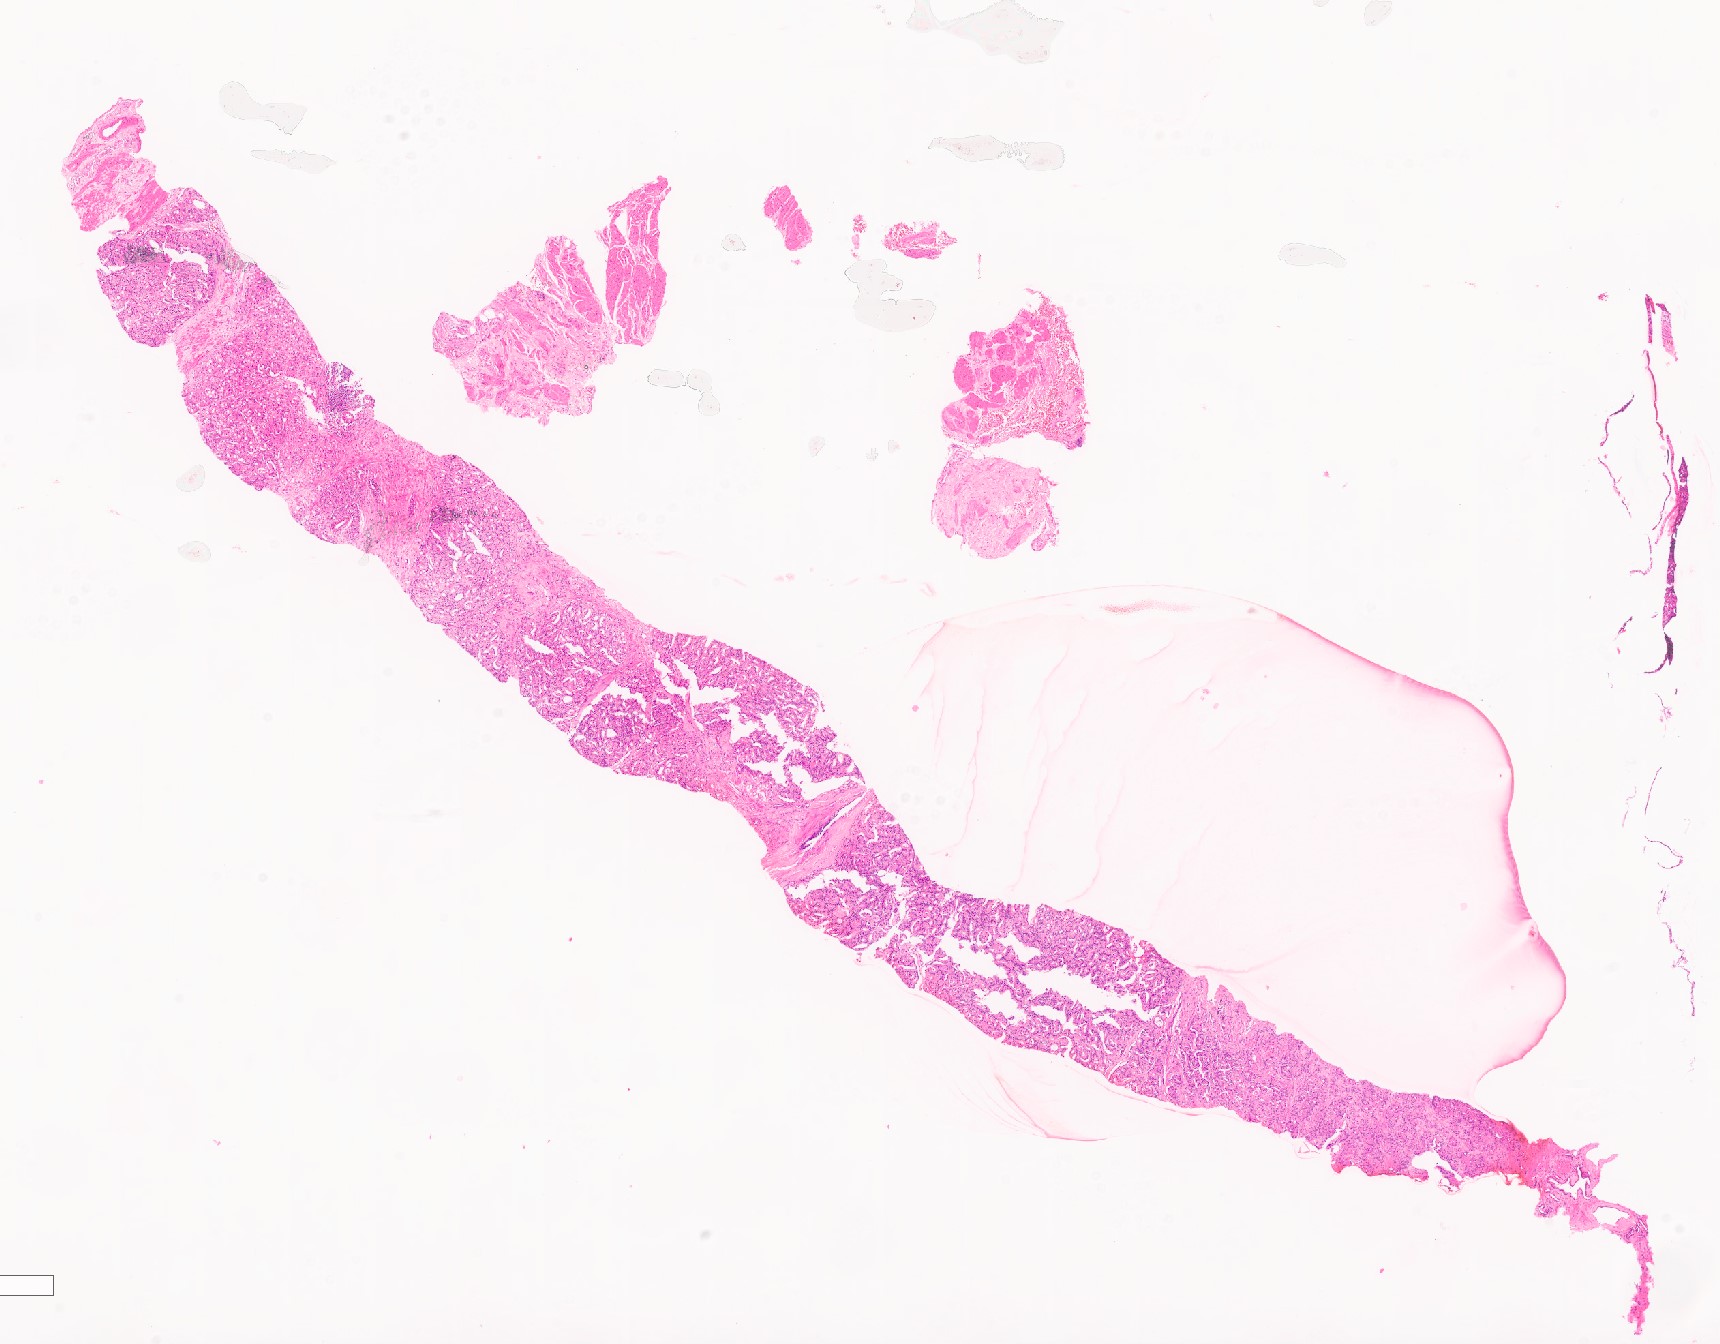

Örnek Rutin Vakalar

patolojiatlasi.com